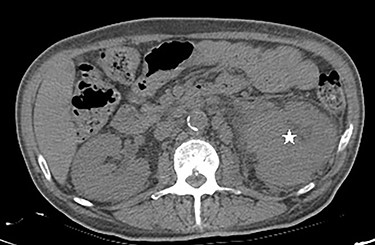

Computed tomography (CT) scan of the abdomen and pelvis showed poorly marginated soft tissue mass centered at the left renal pelvis (Fig. 3). Multiple prominent and enlarged retroperitoneal lymph nodes are noted. Additional CT chest imaging excluded other metastatic lesions.